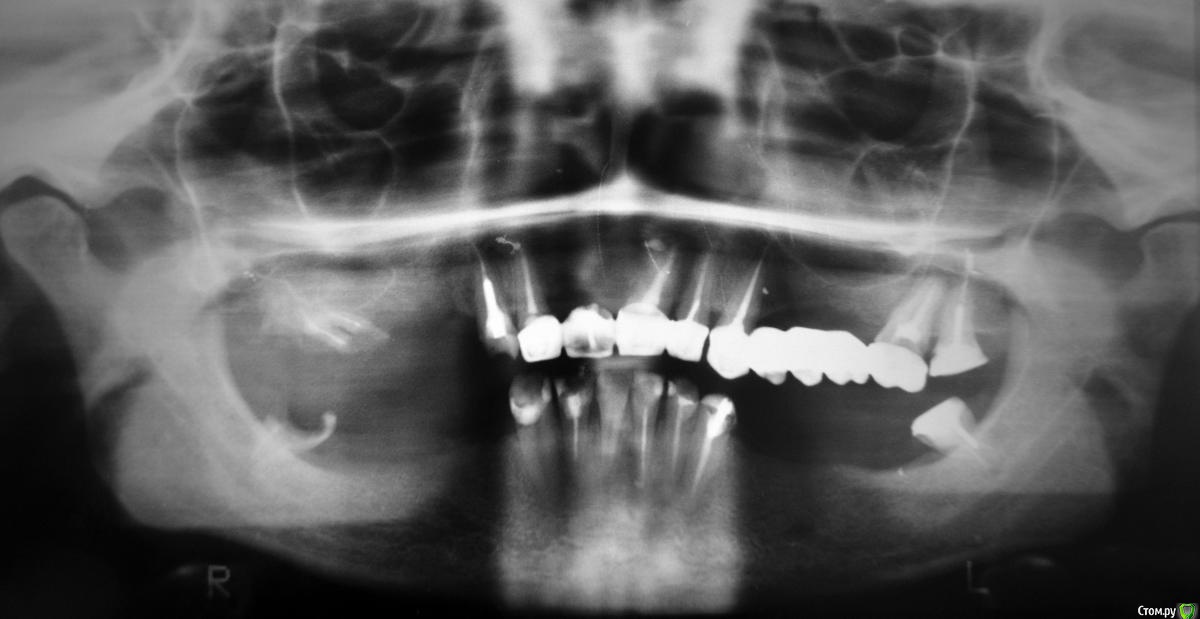

Buuuka Опубликовано 4 июля, 2015 Поделиться Опубликовано 4 июля, 2015 Здравствуйте! Ситуация с зубами плачевная. Нет ни одного зуба, который бы не подвергался лечению. Да и вообще от зубов мало, что осталось. Сверху было 3 мостика. Один отвалился вместе с опорными зубами, которые под ним и разрушились. Тот, что остался слева держится буквально на одном клыке, т.к. второй зуб опорный тоже разрушается. Мостик, естественно, очень сильно шатается. Интересуют вопросы: 1. какие варианты протезирования в такой ситуации ещё возможны (если исключить имплантацию)? 2. Если снять тот мост, который шатается, можно ли спасти те 2 зуба, которые под ним?3. Возможно ли протезирование на телескопических коронках и вообще их установка на такие зубы (если не делать импланты)?4. Возможно ли поставить протез акри-фри? И стоит ли такой ставить вообще?5. Консультировалась у одного ортопеда, он предложил все штифты заменить на более длинные и стекловолоконные и на нижнюю челюсть поставить один сплошной несъёмный мост. Я ошибаюсь, или этот вариант опасен тем, что очень скоро от зубов под таким мостом вообще ничего не останется? Вообще, что ещё есть шанс сделать? Спасибо за внимание. (Уточняю: сломанный правый клык и нижний правый зуб мудрости, от которого отвалилась пломба, восстановлены на данный момент. В них штифты. Восстановлены без гарантии, т.к. на такие зубы гарантию дать невозможно, по словам стоматологов. Всё остальное так и осталось, как на снимке). Снимок: Ссылка на комментарий

Buuuka Опубликовано 12 июля, 2015 Автор Поделиться Опубликовано 12 июля, 2015 Здравствуйте ещё раз. Никто не ответил в теме... У меня случай, в котором уже ничего не сделать? Позавчера сходила к другому ортопеду. Он сказал, что мосты, естественно, надо незамедлительно снимать, т.к. они метало-пластмассовые и отравляют организм и вообще портят оставшиеся зубы и дёсны. Посоветовал сделать 3D снимок. Сказал, что с частью оставшихся зубов надо попрощаться после снятия мостов, в том числе с первым верхним... Неужели и его не сохранить??? Телескопические протезы не советует - говорит, что это всё реклама, а на деле, они тяжелы для зубов и быстро их окончательно разрушат. Бюгель на аттачментах тоже не советует - по той же причине. Разумеется, предложил имплантацию, но, к сожалению, это не мой вариант... Что же остаётся? Только бюгель на кламмерах? Скажите, пожалуйста, что думаете? Можно ли что-то сохранить ещё? Какой протез разумнее выбрать? 3D снимок стоит делать или и без него всё ясно? 1 Ссылка на комментарий

Buuuka Опубликовано 18 июля, 2015 Автор Поделиться Опубликовано 18 июля, 2015 И снова здравствуйте. Сделала 3D снимок. Обнаружилось, что почти везде каналы слишком далеко запломбированы (делалось это всё без рентгена, на глаз...), в одном зубе пломбировочный материал ушёл в гайморову пазуху... Этот зуб советуют удалить по этой причине, хотя он меня не беспокоит.(... Неужели нельзя не удалять? Чем это грозит? Ортопед хочет удалить все оставшиеся 8-ки, оставить только передние зубы сверху и снизу и на все надеть коронки (металлокерамику или цельнокерамические). А уже потом решать, какой съёмный протез ставить. Прокомментируйте такое решение, пожалуйста? Можно ли оставить 8-ки, просто не использовать их в протезировании, но и не удалять? Не знаю, можно ли тут как-то продемонстрировать 3D снимок. Он у меня на диске есть. Всё ещё надеюсь на ваш ответ... Живу в маленьком посёлке и ездить в областной центр мне очень далеко, не хотелось бы ещё и не к тому врачу попасть и не то сделать. Дело в том, что я уже много раз делала всё не так, как надо. Например, лишилась как минимум 4 зубов просто потому что у нас тут в поликлинике нет рентгена, не используются штифты и т.п. и восстанавливать зубы могут только в самых простых случаях... мне просто их вырвали и всё. Попасть в город я на тот момент физически не могла. А о том, что были большие шансы все эти зубы сохранить даже не подозревала. Позже, когда получилось поехать хотя бы в районный центр, я попала в клинику, в которой мне вот так "удачно" всё запломбировали... тоже без снимков, зато с металлическими штифтами, которые теперь мне советуют вытаскивать и менять на стекловолокно. Ссылка на комментарий

doca Опубликовано 19 июля, 2015 Поделиться Опубликовано 19 июля, 2015 И снова здравствуйте. Сделала 3D снимок. Обнаружилось, что почти везде каналы слишком далеко запломбированы (делалось это всё без рентгена, на глаз...), в одном зубе пломбировочный материал ушёл в гайморову пазуху... Этот зуб советуют удалить по этой причине, хотя он меня не беспокоит.(... Неужели нельзя не удалять? Чем это грозит? Ортопед хочет удалить все оставшиеся 8-ки, оставить только передние зубы сверху и снизу и на все надеть коронки (металлокерамику или цельнокерамические). А уже потом решать, какой съёмный протез ставить. Прокомментируйте такое решение, пожалуйста? Можно ли оставить 8-ки, просто не использовать их в протезировании, но и не удалять? Не знаю, можно ли тут как-то продемонстрировать 3D снимок. Он у меня на диске есть. Всё ещё надеюсь на ваш ответ... Живу в маленьком посёлке и ездить в областной центр мне очень далеко, не хотелось бы ещё и не к тому врачу попасть и не то сделать. Дело в том, что я уже много раз делала всё не так, как надо. Например, лишилась как минимум 4 зубов просто потому что у нас тут в поликлинике нет рентгена, не используются штифты и т.п. и восстанавливать зубы могут только в самых простых случаях... мне просто их вырвали и всё. Попасть в город я на тот момент физически не могла. А о том, что были большие шансы все эти зубы сохранить даже не подозревала. Позже, когда получилось поехать хотя бы в районный центр, я попала в клинику, в которой мне вот так "удачно" всё запломбировали... тоже без снимков, зато с металлическими штифтами, которые теперь мне советуют вытаскивать и менять на стекловолокно. Здравствуйте, никто не отвечает, по всей видимости потому, что очень уж неоднозначная ситуация и многое определяется только после очной консультации, снятия коронок ,удаления пораженнных кариесом тканей зубов.Может быть и такое,что все зубы верхней челюсти нужно удалять.А так стандартная схема : удаление того ,что нужно удалять, остальное лечить и восстанавливать коронками.Бюгельные протезы лучше ,чем пластиночные, в вашем случае такой скорее всего только на нижнюю челюсть.В безметалловых коронках в Вашем случае лично я смысла не вижу.,а анкерные штифты менял бы не на стекловолокно ,а на литые внутрикорневые вкладки.(опять же если зубы подлежат сохранению) 1 Ссылка на комментарий